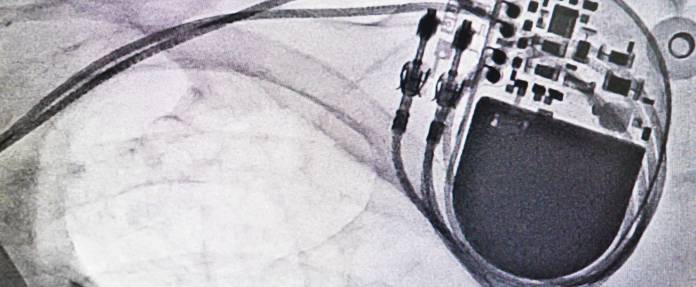

Im medizinischen Alltag lässt sich anhand der Untersuchungen planen, wann eine HSM-Batterie ausgetauscht werden muss. Die Kontrolltermine lassen ersehen, ob die Batterie des Schrittmachers in absehbarer Zeit verbraucht ist. Rechtzeitig vorher erhält der Patient einen Termin zum Austausch des Herzschrittmachers. Die Batterie ist ein fester Bestandteil des HSM. Daher wird ein komplett neuer HSM eingebaut und an die alten Elektroden angeschlossen.

Liegen keine Auffälligkeiten vor, dauert der Ersatz eines Herzschrittmachers maximal eine Stunde. Die bestehende Haut-Tasche unterhalb des Schlüsselbeins wird geöffnet und der alte HSM von den Elektroden abgekoppelt. Diese werden auf ihre Funktionstüchtigkeit überprüft. Das neue Gerät lässt sich schnell anschließen und nimmt seine Arbeit auf.